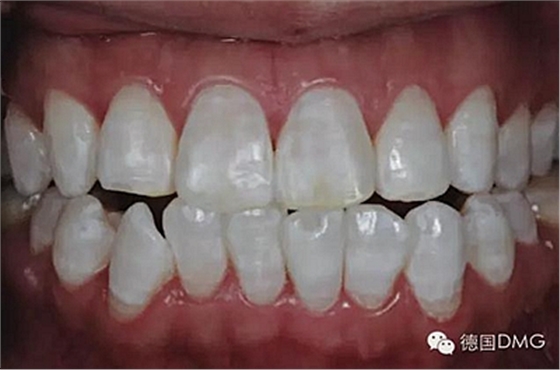

5、由于氟斑牙存在釉質(zhì)礦化不全等問題,家庭漂白兩周后,使用標(biāo)準(zhǔn)的樹脂滲透技術(shù) (Icon, DMG Products, Hamburg. Germany) 來預(yù)防釉質(zhì)齲。最后,徹底改變患者的前牙美學(xué),并在一年后仍保持穩(wěn)定。

利用釉質(zhì)打磨技術(shù)聯(lián)合牙齒漂白和樹脂滲透技術(shù)的微創(chuàng)方法是治療重度氟斑牙的有效方式。同時(shí),這一技術(shù)費(fèi)用低、省時(shí)間。